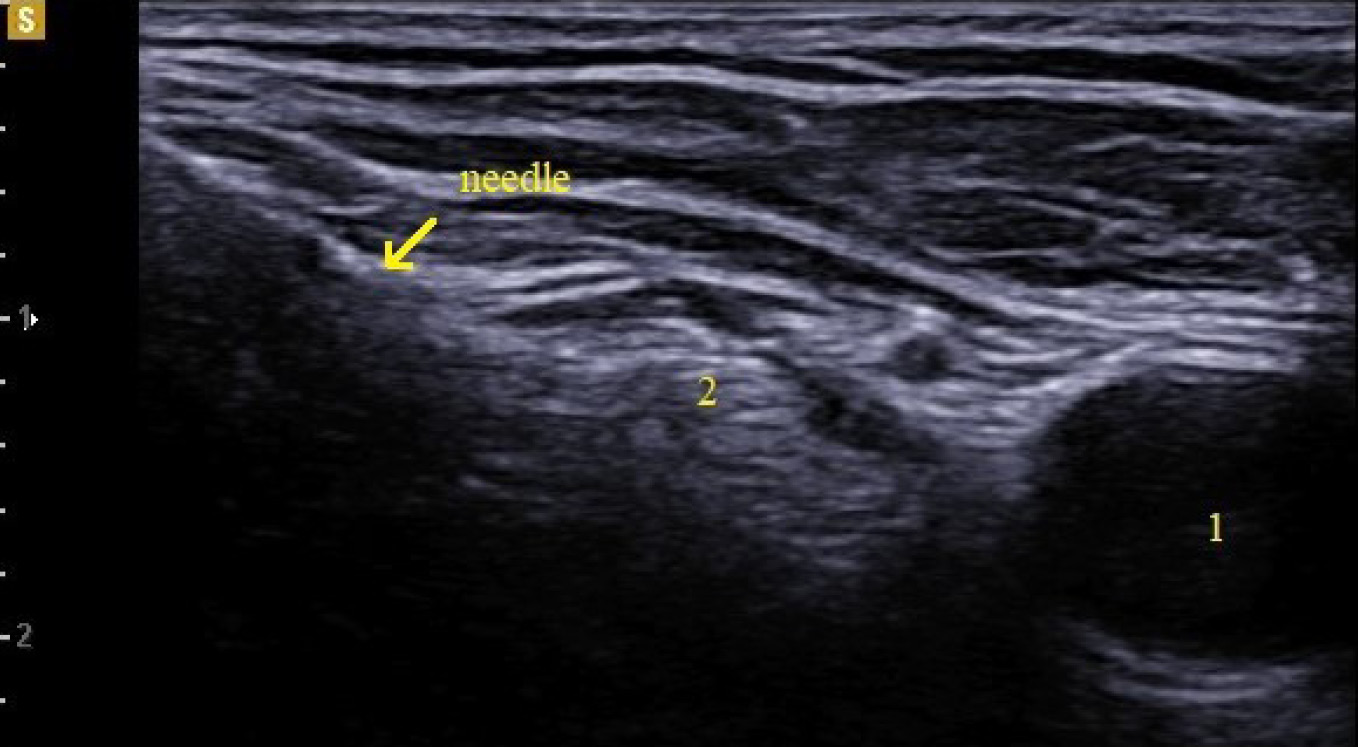

Using a catheter-through-needle technique, a perineural catheter was positioned at 2 cm from the femoral nerve (Fig. 3).

Fig. 3. Femoral nerve catheter.

Note. 1 — femoral artery, 2 — femoral nerve.